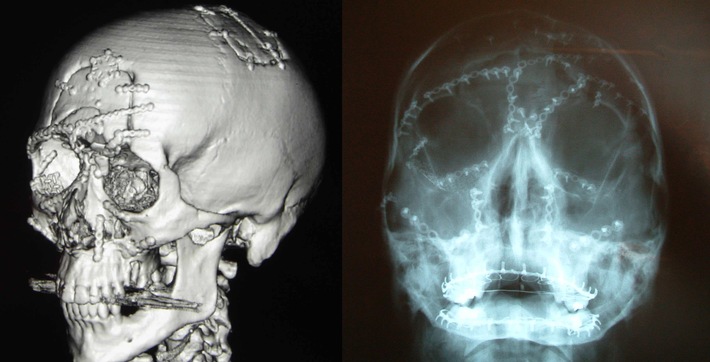

Aux HUG, Gavin a subi une opération de 19 heures, pratiquée par le

professeur Michel Richter - spécialiste en chirurgie maxillo-faciale

- et son équipe. Gavin souffrait notamment de sérieuses fractures

multiples du crâne, de l'os frontal, du nez, des orbites, de

l'ethmoïde, de la région malaire et de la base crânienne antérieure,

ainsi que de lésions au cerveau et à la jambe.

Les blessures à la tête de Gavin étaient si importantes que les

chirurgiens ont dû faire usage de près de 130 vis et 21 plaques -

record absolu en Europe. Gavin a été opéré selon les principes et

techniques éprouvées de la Fondation AO.

"M. Sugar et son équipe de l'hôpital Morriston ont travaillé en

étroite collaboration avec l'équipe des applications médicales à

l'University of Wales Institute, Cardiff (UWIC), et utilisé des

scanners 3D de haute technologie pour préparer mes interventions

chirurgicales. Le suivi chirurgical et les soins après intervention

que j'ai reçus à l'hôpital étaient exceptionnels" explique Gavin.